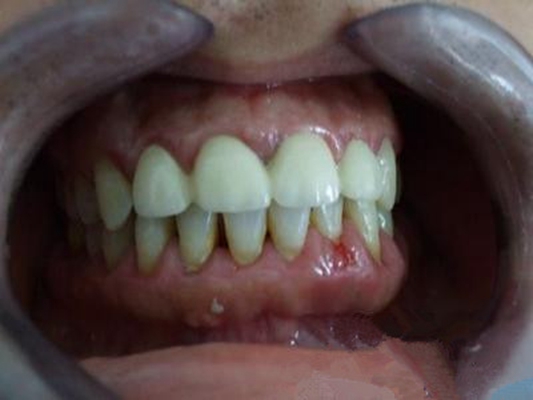

牙周炎圖片

牙周袋 (8)